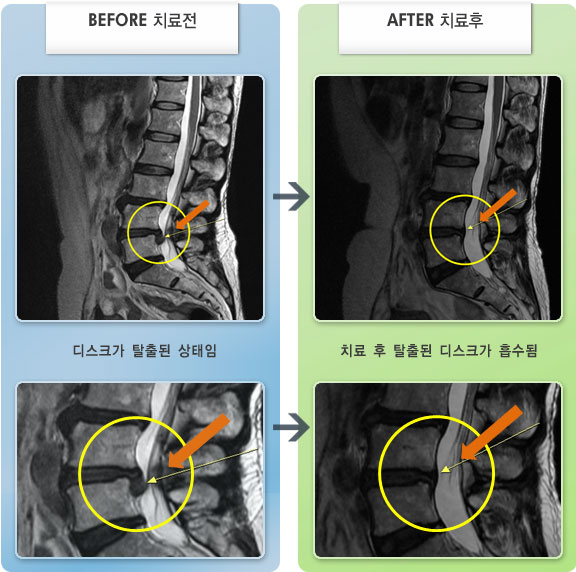

Before

After

허리통증이 심해서 숙이기 어렵고 차에서 내리기 힘들었습니다.

2021.01.06 ~ 2025.03.10

Before

After

허리 통증과 우측 허벅지 통증 및 저림 증상 지속되어 내원하셨습니다.

2022.08.20 ~ 2024.11.08